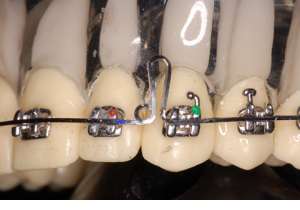

De modo geral, as descompensações são realizadas às custas de extrações e projeções dentárias nos arcos antagônicos. Nas Classes III, as extrações recaem sobre os pré-molares superiores e na projeção dos incisivos inferiores. Nas Classes II, a situação inversa irá ocorrer, com a extração dos pré-molares inferiores e a vestibularização dos incisivos superiores. Diante desse quadro, torna-se primordial explicar aos pacientes e seus responsáveis que durante esse processo as discrepâncias esqueléticas se tornarão mais evidentes, o que irá piorar temporariamente o aspecto facial do paciente. O reequilíbrio da face só acontecerá após a cirurgia ortognática.

O primeiro passo, ao se planejar esses casos, consiste em reposicionar os incisivos numa angulação mais próxima do ideal possível em relação às suas bases ósseas. Dessa forma, podemos levar em consideração as avaliações cefalométricas do longo-eixo dos incisivos superiores com o plano palatino (1.pp) e dos inferiores com o plano mandibular (IMPA). Embora outras medidas cefalométricas possam ser utilizadas nessa avaliação, considerar a boa relação dente-osso nos parece bem mais óbvio nesse momento e quantifica o movimento necessário para a sua descompensação.